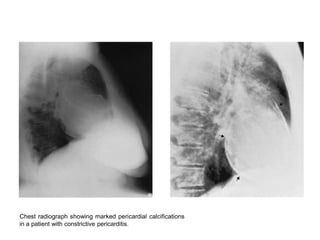

   The cardiac silhouette can be enlarged secondary to a coexisting pericardial

   Pericardial calcification is seen in a minority of patients and should raise the

   The lateral chest film is useful to detect pericardial calcification along the right

heart border and in the atrioventricular groove.

Chest radiograph showing marked pericardial calcifications

in a patient with constrictive pericarditis.